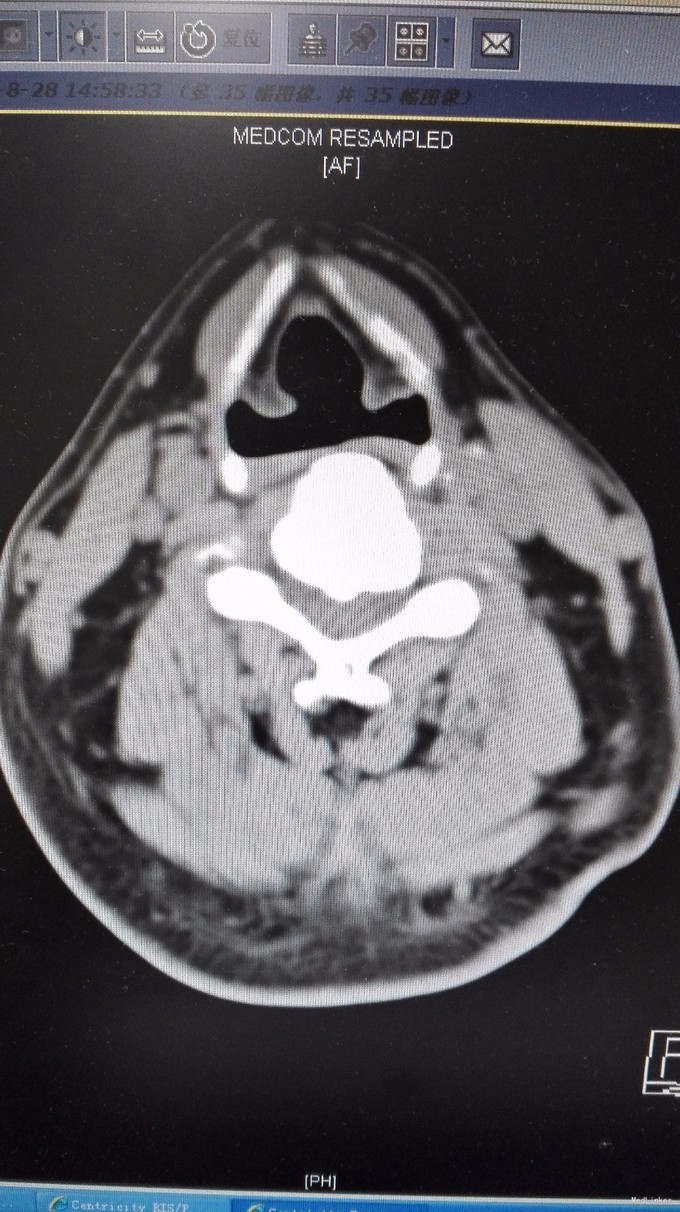

查体:双手麻木感,肱三头肌肌腱反射活跃,左侧髂腰肌4级,臂丛牵拉实验阴性,椎间孔挤压实验阴性。 辅查:CT:C2-7椎间盘突出,继发性椎管狭窄,OPLL,OFL。

诊断:混合型颈椎病(脊髓型+神经根型) 治疗:颈后路3-7单开门椎管扩大成型术(锚定法)